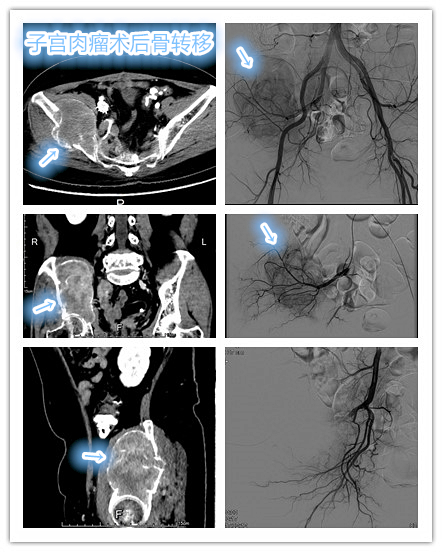

典型病例

中年女性,子宫内膜间质肉瘤术后骨转移(Ⅳ期),经多程姑息化疗无效,髂骨转移瘤进行性增大,出现髋部及下肢疼痛、麻木不适。依据病灶特点,为患者制定个体化介入治疗方案:局部动脉化疗栓塞+局部射频消融治疗,先通过化疗栓塞骨转移瘤阻断其营养供血,再后续局部热消融毁损肿瘤病灶,使得短时间内有效控制杀灭肿瘤,改善相关症状。

局部动脉化疗栓塞治疗:有效阻断肿瘤的营养血供,促进肿瘤坏死萎缩。

骨转移瘤射频消融治疗:局部高温烤死肿瘤组织,快速杀灭肿瘤细胞。